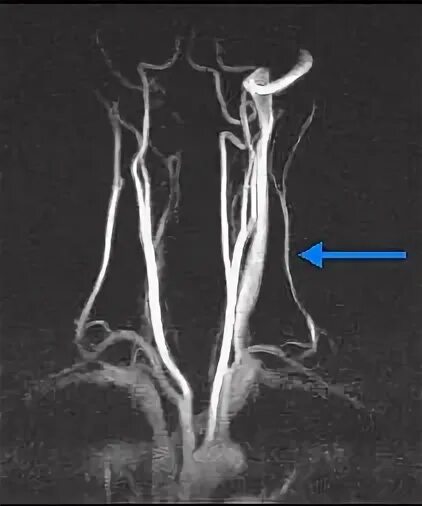

Гипоплазия сегмента v4 позвоночных артерий